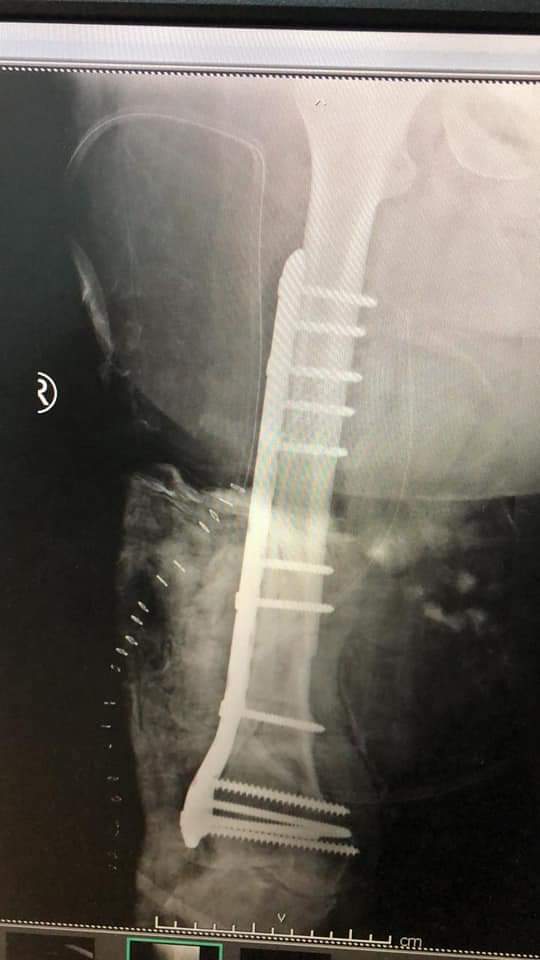

حيث تمكن قسم الجراحة الخاصة / شعبة العظام في المستشفى من إجراء عملية نوعية لمريض يعاني من وجود ورم رخوي خبيث ضخم في الفخذ الايمن بالاضافه لتعرضه لكسر في عظمه الفخذ .

وأجرى العملية فريق طبي بإشراف إستشاري جراحة أورام العظام الدكتور زياد مهيدات حيث استغرقت العملية الجراحية (6) ساعات وتعتبر هذه العملية من العمليات المعقدة والصعبة ،حيث أظهرت الأشعة ضخامة الورم وقربه الشديد من الاوعية الدموية والاعصاب الرئيسية المغذية للساق .